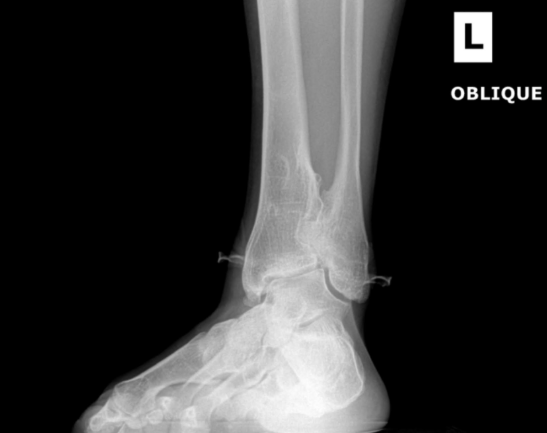

Ankle fracture repair

AF2